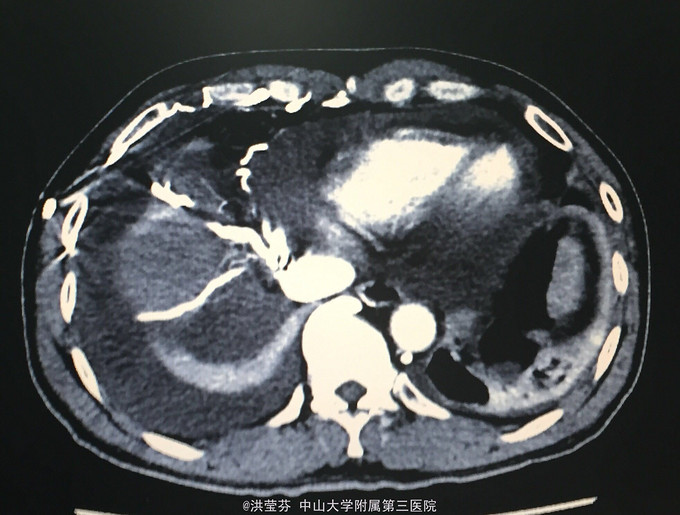

查体:KPS 60分,BSA 1.83m2,T 38.5℃,全身浅表淋巴结未触及明显肿大,胸壁可见浅表静脉曲张,呼吸急促,左下肺、右中下肺呼吸音明显减弱,其余肺野呼吸音促,可闻及少许实性啰音,心率110bpm,律齐,腹软,全腹无压痛、反跳痛,未扪及明显包块,肝脾肋下未触及,移动性浊音(——),肠鸣音正常,4次/分,双下肢无凹陷性水肿。 辅助检查:血常规无特殊,生化转氨酶稍升高,低钠低氯,CRP 227.9mg/L,凝血四项:Fib 8.14g/L。复查胸部CT提示:1.胸腺癌并纵膈淋巴结及双肺多发转移瘤,右心房、上腔静脉受侵并癌栓形成,病变较前进展。2.双肺炎症,以右肺为著。3.双侧胸腔及心包积液。上腹部CT提示:1.下腔静脉早显并肝表面多发侧支形成,考虑右心流出道阻塞所致;腹壁静脉曲张。头颅MR提示右侧颞叶强化灶,结合病史,考虑转移瘤,伴瘤灶少量出血可能,瘤周脑水肿。